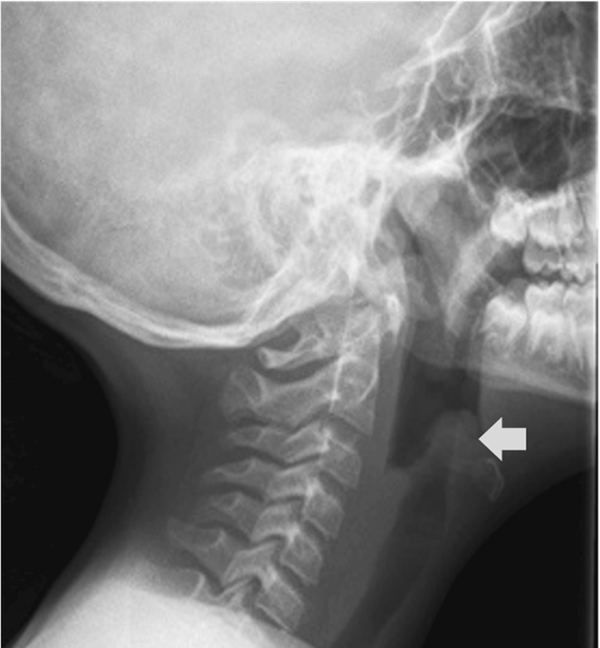

(图1 颈部侧位X线片显示"拇指"征)

会厌炎的诊断主要通过临床评估,强调早期症状识别的重要性。Hib 会厌炎起病急、症状迅速恶化,常见的表现包括中毒症状、呼吸窘迫、高热、咽喉痛、吞咽困难、声音低沉、流涎和喘鸣。为维持气道通畅,患儿只能端坐呼吸,躯干前倾、颈部过伸和下颚前探(即“三脚架”姿势)。本例患儿入院时的主诉是急性胸痛和呼吸急促,没有表现出声音低沉或喘息。但由于高热,中毒症状,呼吸窘迫,咽喉痛和“三脚架”姿势,疑似会厌炎。

影像学检查对于会厌炎的诊断并不是必需的,也不应该延误治疗。考虑到即将发生上气道阻塞的风险,会厌炎患者的迅速稳定和气道管理至关重要。在本例中,患儿立即接受了高流量氧气面罩的支持,由于气道保持稳定,无恶化迹象,因此不需要紧急插管。 根据推荐并考虑到潜在病原体的谱(流感嗜血杆菌、